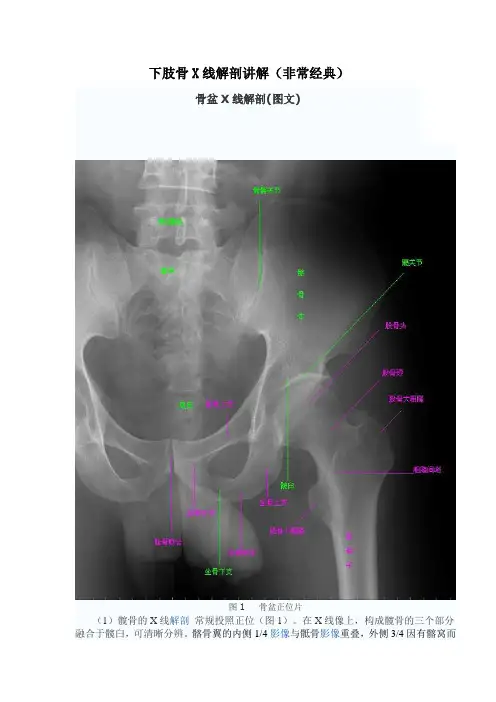

下肢骨X线解剖讲解(非常经典)骨盆X线解剖(图文)图1 骨盆正位片(1)髋骨的X线解剖常规投照正位(图1)。

在X线像上,构成髋骨的三个部分融合于髋臼,可清晰分辨。

髂骨翼的内侧1/4影像与骶骨影像重叠,外侧3/4因有髂窝而较透亮。

髂嵴阴影较致密,边缘不光滑,外侧可见髂前上棘影,髂后上棘则重叠于骶骨影内。

弓状线及骨盆腔内侧壁形成复合影像,外侧可见弧形的髋臼阴影。

髋臼阴影的上段粗而致密,中段较细,它向下绕过髋臼切迹前部的下缘,与耻骨体的内面形成一条“U”形的致密线,称为泪滴线(Koekler泪滴),泪滴线二脚之间的距离,即髋臼窝的厚度。

髋臼内下方的透亮影为闭孔。

闭孔影的上界是耻骨上支、外侧界是坐骨体的下份,坐骨结节阴影与其重叠。

坐骨棘的阴影呈三角形突向盆腔。

(2)骨盆的X线解剖骨盆一般投照前后位,检查骶、尾骨时可加照侧位,检查骶髂关节时应加照45°斜位,产科骨盆测量另有其特殊投照方法。

骨盆前后位片上,骶骨中线应通过耻骨联合。

骶髂关节左右对称,关节间隙下半部分可以显示,上半部常投影出模糊双线影。

界线的影像在女性呈卵圆形,在男性略呈鸡心形。

髂嵴连线影正好通过第4、5腰椎间隙。

由髂嵴影向外可追踪到骼前上、下棘,由髂前下棘到股骨颈外上缘的连线称髂颈线,用以判定髋关节是否正常。

正位片上,可以测量耻骨下角,男性为锐角,女性为钝角。

女性骨盆径线的测量,可以采用正位(见图1)和侧位。

正位片上,界线影像最远点连线为入口横径,正常为12.3cm;两侧坐骨棘连线为中骨盆横径,正常为10.5cm;两侧坐骨结节间距为小骨盆出口横径,正常为11.8cm。

侧位片上,耻骨联合后缘上端到骶骨岬连线为小骨盆入口前后径,正常为11.6cm;耻骨联合后缘下端和坐骨棘中点的连线延长到骶骨的前缘,为中骨盆前后径,正常12.2cm;耻骨联合后下缘到骶尾关节的连线,为小骨盆出口前后径,正常11.8cm。